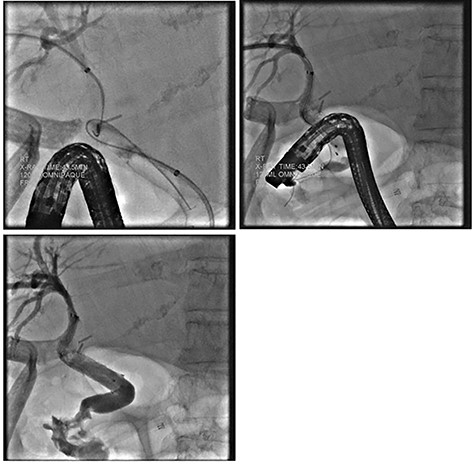

Despite external drainage, the patient experienced persistent bilious output from the JP drain. A rendezvous procedure was performed; cholangiography visualized the dilated bilateral intrahepatic ducts with narrowing at the proximal CBD. Via a simultaneous endoscopic approach, the distal CBD was successfully cannulated and balloon dilated. A 10 x 60 mm covered fluency (BARD) stent was deployed. Completion cholangiogram demonstrated contrast flowing to the duodenum with no extravasation. The patient recovered well and was subsequently discharged (Fig. 2).

ERCP demonstrating successful rendezvous with deployment of metal stent in the vicinity of surgical drain.